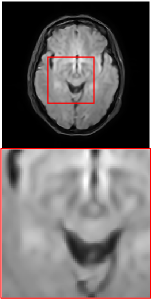

Figure 5 provides the qualitative comparison of the various methods on the four datasets at a scale of 4. The top, second, third, and bottom rows are the SR results under the FastMRI, clinical brain, clinical tumor and clinical pelvic datasets, respectively. The red boxes indicate the zoom-in region of complicated anatomical structures along with their corresponding error maps. Note that the brighter textures in the error maps, the lower the quality of the reconstructed images. As can be seen, compared to methods based on Transformers and CNNs, diffusion-based methods like DisC-Diff and DiffMSR (Ours) are capable of reconstructing high-realistic images with promising reconstruction metric scores (PSNR and SSIM). Nevertheless, while DisC-Diff can reconstruct high-precision MR images, it does not preserve the structure present in the original HR images, introducing some additional information that can affect medical diagnosis. In contrast, our method combines DM and PLWformer, which can preserve the original image’s structure while restoring high-frequency information.

In this section, we present more visual qualitative comparisons. Figures 8, 9, 10, and 11 show the reconstruction results of each method in FastMRI, clinical brain, clinical tumor, and clinical pelvic, respectively. As can be seen, although DisC-Diff can reconstruct MR images with high-frequency information, it fails to preserve the structure and content of the original Target HR image effectively, resulting in image distortion. In contrast, our proposed DiffMSR can restore high-frequency information while preserving the structure of the original HR image, indicating the effectiveness of the joint use of DM and PLWformer.